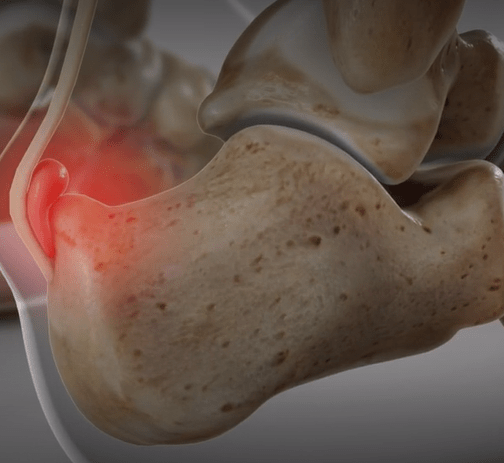

Pain with palpation above and anterior to Achilles insertion and swelling on both sides of the heel cord. Two words in the name.

Retrocalcaneal Bursitis